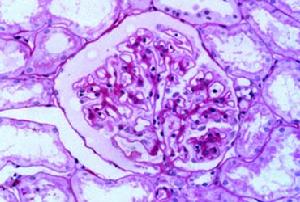

雙腎狼瘡性腎病是指系統性紅斑狼瘡合併雙腎不同病理類型的免疫性損害,同時伴有明顯腎臟損害臨床表現的一種疾病。

狼瘡性腎病(二)多數有中度貧血,偶呈溶血性貧血、血白細胞下降,血小板多數少於100×109/L,血沉較快。

(三)免疫學檢查:血清多種自身抗體陽性,γ-球蛋白顯著增高,血循環免疫複合物陽性,低補體血症,尤其在活動期。血紅斑狼瘡細胞陽性,皮膚狼瘡帶試驗陽性。

(四)重型活動性狼瘡性腎炎伴有可逆性的Ccr不同程度下降、血尿素氮和肌酐升高、血白蛋白降低或肝功轉氨酶增高;終末期狼瘡性腎炎Ccr明顯下降和血肌酐、尿素氮顯著升高。

一、狼瘡性腎炎的治療基於臨床表現、實驗室和腎活檢資料。對於輕症系統性紅斑\r\n狼瘡(如僅有皮疹、低熱或關節症狀等)和免疫血清學檢查異常,若尿檢正常、腎活檢顯示腎小球正常或輕微病變者,酌情用非甾體類抗炎藥改善症狀,一般無需用糖皮質激素或細胞毒藥物,密切追蹤病情變化;若尿檢異常、腎活檢顯示腎小球局灶節段性系膜增生伴有節段性壞死、新月體形成及局灶性腎小球硬化者,用中、小劑量糖皮質激素(如強的松20~40mg/d),酌情加用細胞毒藥物或雷公藤製劑。